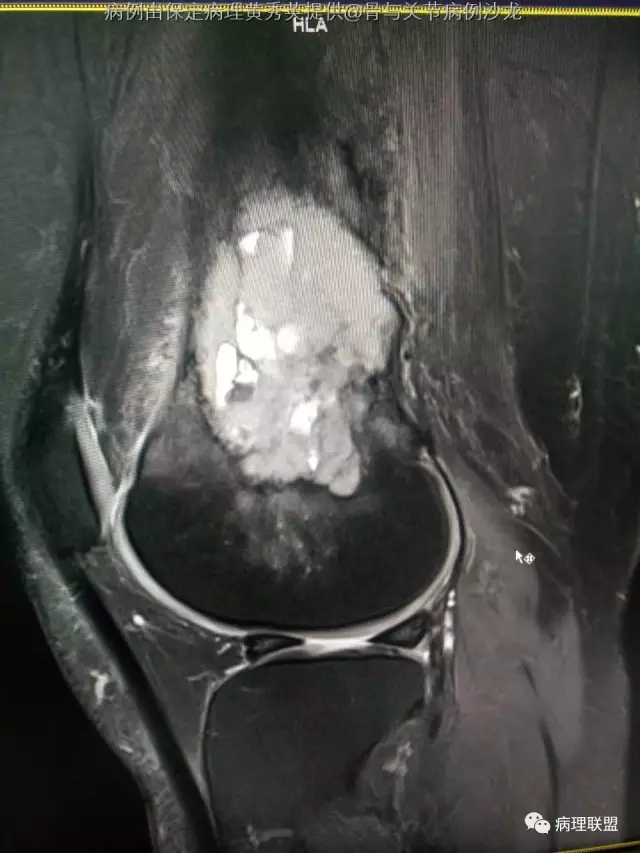

女67岁,股骨下端肿物约6cm,(病例由保定病理黄秀英提供,致谢!)